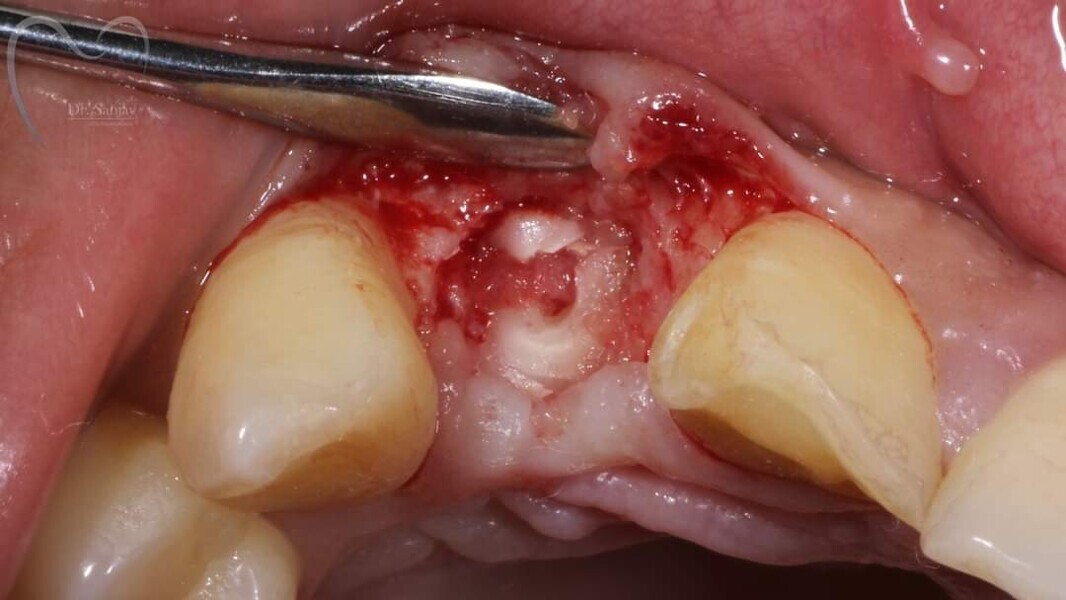

Esthetic Rehabilitation of Maxillary Anterior Teeth: Dr Sanjay Sah